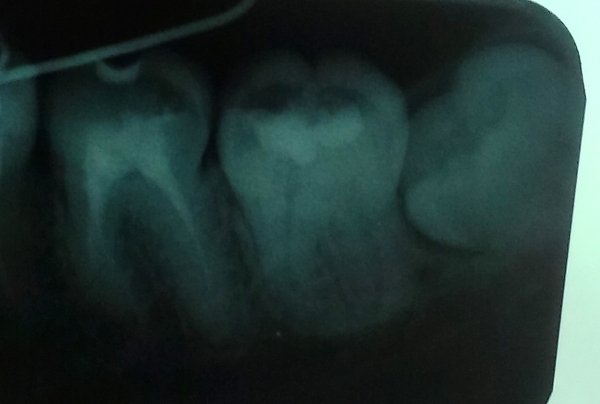

Растет зуб мудрости в соседний зуб. Сдавил корень, это хорошо видно на снимке. Десна не болит, но воспалился под челюстной лимфоузел, отдает в ухо такая не постоянная боль. Лимфоузел уже полгода не проходит. Стоит ли удалять?

• Зуб подлежит удалению. Ситуация может усугубиться, так как зуб очень давит на соседнюю семерку. Могут начать сдвигаться другие зубы, будет присутствовать болезненность. Может затруднится открывание рта. Лучше с удалением не затягивать.